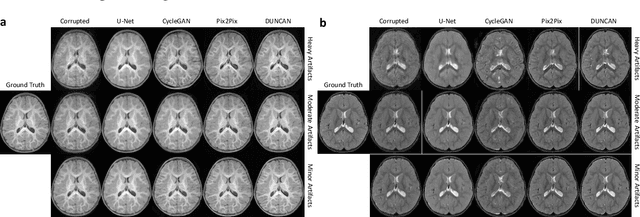

Abstract:Retrospective artifact correction (RAC) improves image quality post acquisition and enhances image usability. Recent machine learning driven techniques for RAC are predominantly based on supervised learning and therefore practical utility can be limited as data with paired artifact-free and artifact-corrupted images are typically insufficient or even non-existent. Here we show that unwanted image artifacts can be disentangled and removed from an image via an RAC neural network learned with unpaired data. This implies that our method does not require matching artifact-corrupted data to be either collected via acquisition or generated via simulation. Experimental results demonstrate that our method is remarkably effective in removing artifacts and retaining anatomical details in images with different contrasts.